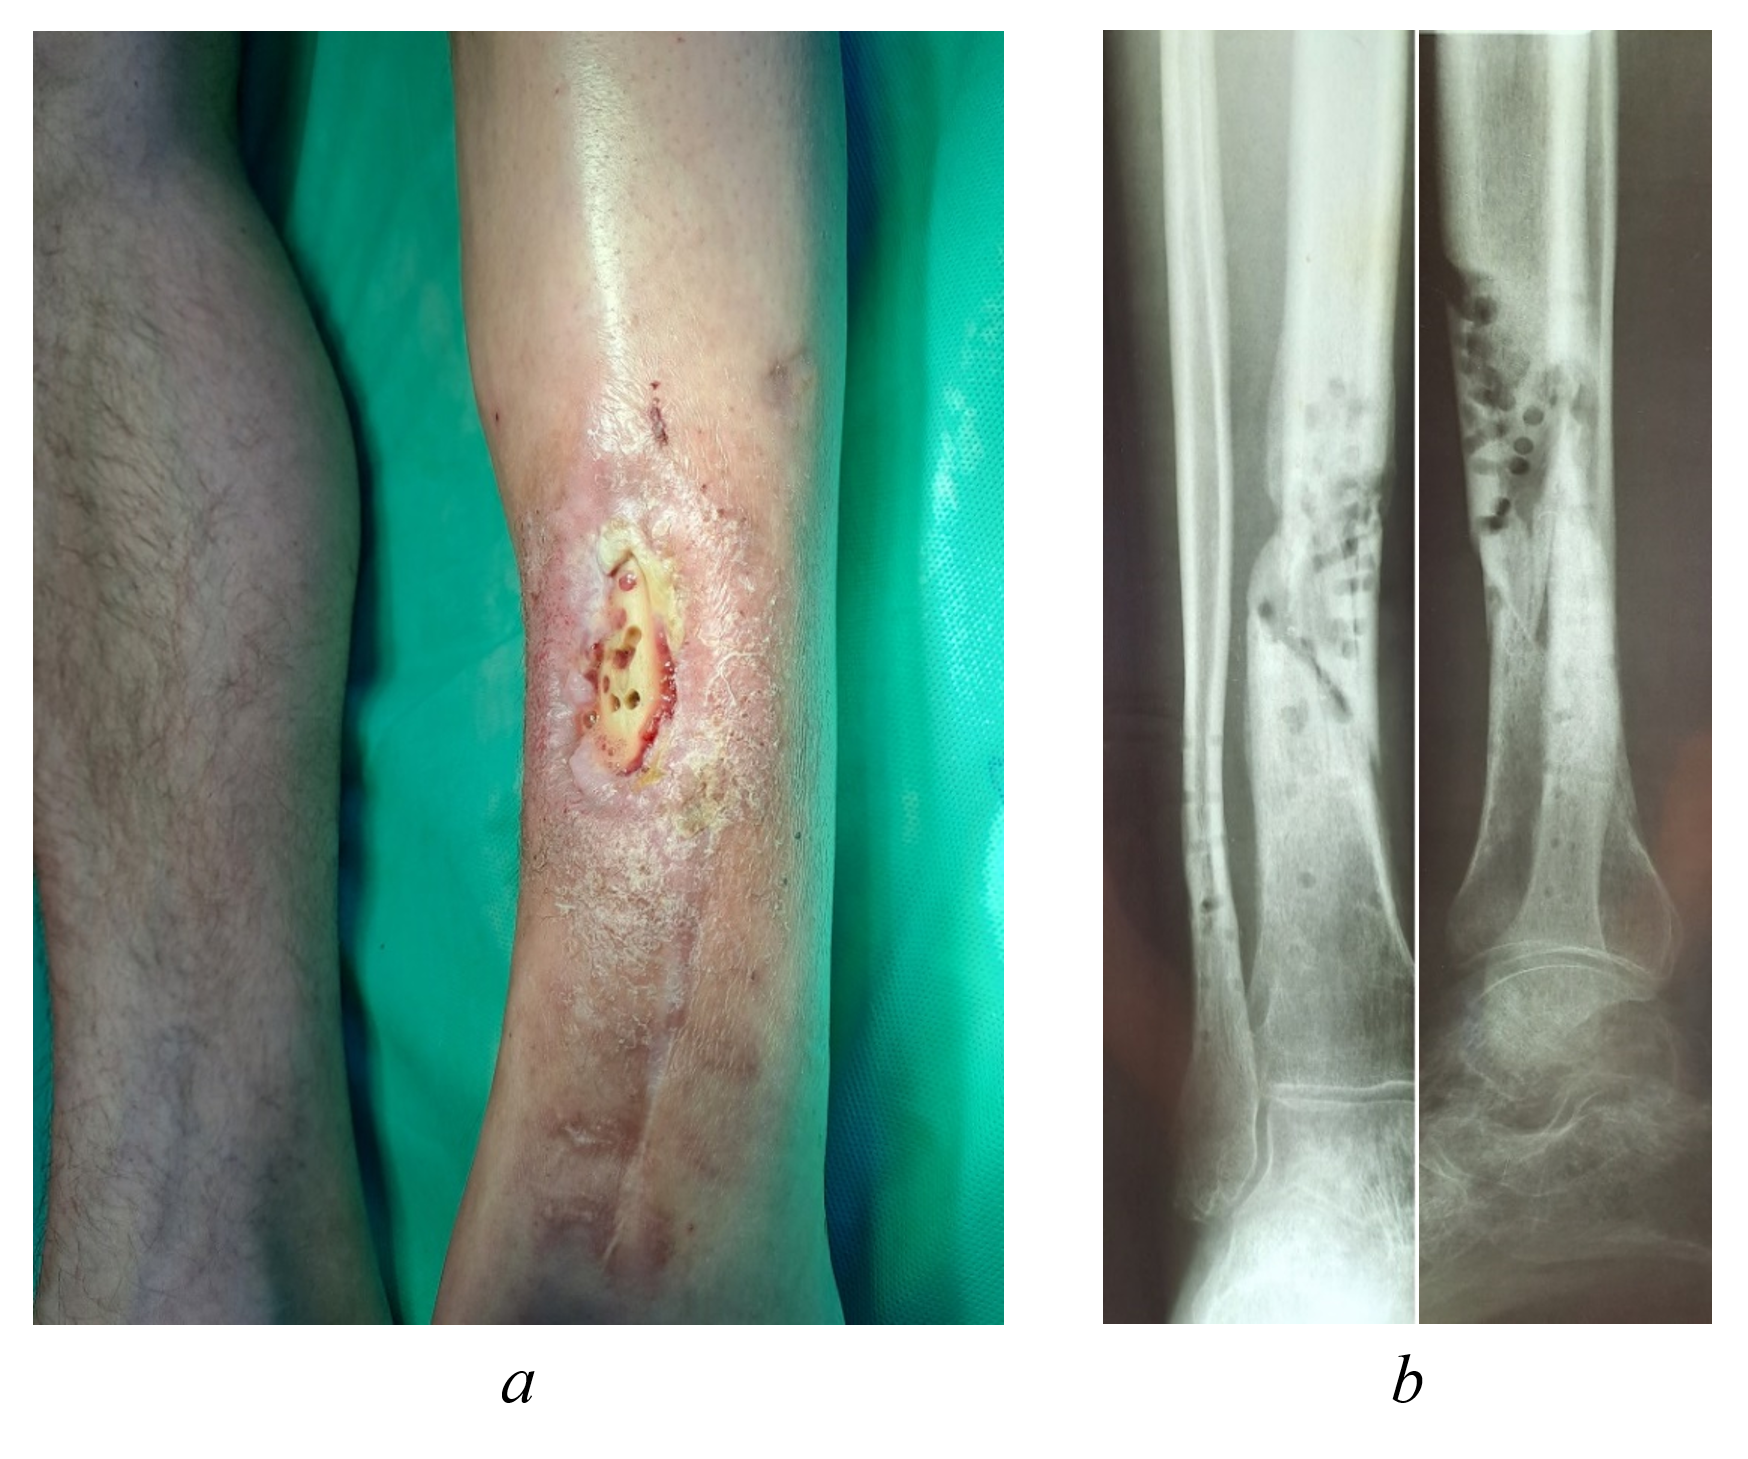

The left shin showed no edema or erythema. On the anterior surface of its middle third, there was a 6 × 2 cm skin and soft tissue defect with scanty purulent discharge. The base of the defect consisted of ulcerated grayish tibial bone with multiple osteoperforation fenestra (Figure 1a). Pathological mobility of the shin was evident in the area of the trophic ulcer. Range of motion in the joints of the left lower extremity remained intact, with preserved sensation. Peripheral pulses (dorsalis pedis, popliteal, and femoral arteries) were palpable. No signs of venous insufficiency were detected.

Figure 1 - External appearance (a) and radiograph (b) of the left shin of patient Yu., 43 years old, upon admission to the Clinics of SamSMU